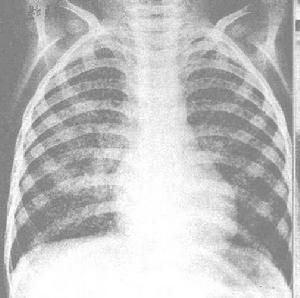

肺諾卡菌病X線圖起病緩急不一。免疫功能低下者常呈急性起病。全身症狀有發熱,疲乏無力,厭食等。呼吸道症狀有咳嗽,黏稠膿痰,量通常不多,胸痛,氣急,咯血等。胸壁有時可見瘺管。不治療或治療延誤則轉成慢性,出現類似肺結核病的慢性感染的相應表現。胸部X線呈現炎症浸潤、實變、單發或多髮結節狀陰影,經常有膿腫和空洞形成,偶見厚壁空洞。病變分布以

臨床症狀初為乾咳,繼之為粘稠膿性痰,後期咳膿臭痰,痰中可帶血,常有發熱、盜汗、胸痛及消瘦等,體溫多為38~C~40~C。可出現胸腔積液或膿胸,少數可穿破胸壁至皮膚形成瘺管,也可波及腹腔、內臟或經血循環播散至全身。x線胸片早期表現為炎性浸潤類似小葉性或大葉性肺炎,也可表現為單發或多髮結節影,可發現厚壁透光區,代表多發性小膿腫形成的空洞。還可伴有肺門淋巴結腫大,但很少有鈣化。病變可累及一葉或多葉。有時呈水皰性或壞疽性改變,表麵皮膚為粉紅色,其後迅速擴展並破潰,其上有粘性黃白色膿液;向周圍擴散後引起全足腫脹,足趾變形。也可向深部組織及骨擴展,形成多數膿腫、相互交通的竇道、瘺管及骨質破壞等。分泌物呈漿液狀、膿性或油狀,常帶白色、黃色或黑色顆粒。病原菌最常播散部位是在大腦引起腦膿腫,其次是在腎臟引起腎膿腫等,也可引起心內膜炎、心肌炎、心包炎,肝、脾、腎上腺、胃腸、淋巴結、肋骨、椎骨、骨盆及關節也可受累,胰腺、甲狀腺、眼、耳、脊椎、垂體及膀胱較少累及。病變以局部膿腫最為常見。臨床感染徵象突出,常有發熱,多部位膿腫,多器官損害,預後不良。臨床診斷本病臨床表現無特異性,如有前述部位感染徵象而排除其他疾病時可考慮本病的可能性。尤其是臨床上同時有“腦瘤”或多發性皮膚膿腫者,更應考慮血行播散性諾卡菌病,及時進行諾卡菌病原學檢查確診。

其他輔助檢查:胸部X 線呈現炎症浸潤、實變、單發或多髮結節狀陰影,經常有膿腫和空洞形成,偶見厚壁空洞。病變分布以兩下葉多見,亦可呈粟粒樣或瀰漫性間質性浸潤,極少鈣化和纖維化,約1/3 患者並發膿胸。